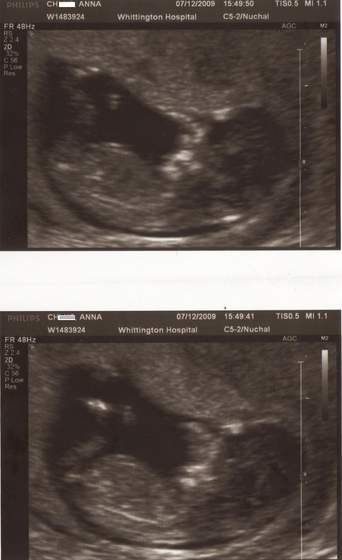

cudne maleństwa